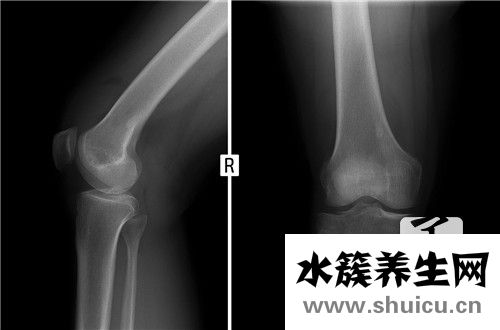

腰椎压迫神经来源于腰4、5神经根和骶1-3神经根,腰椎压迫神经在腘窝之前,分成胫神经和腓总神经,操纵小腿肚及足的所有肌肉及其除隐神经操纵区之外的小腿肚与足的皮肤觉得。

2、腰椎错位造成脚麻

当腰椎失稳、移位或骨盘移位后,腰骶神经过度紧张或被压迫,促使其所操纵的肌肉收缩、筋挛,或其操纵的皮肤觉得而出現酸痛的不适感病症。